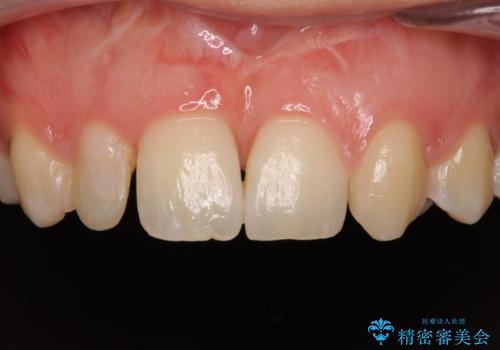

- 他院で矯正治療を終え、上顎前から2番目の歯の大きさを気にして来院された患者様です。

右側は小さく、左側は欠損により犬歯が前から2番に来ている状態でした。

矯正治療の段階で、矮小歯は前後にスペースが作ってあったため、極力左右対称の歯冠形態となるように補綴治療を行うこととしました。

歯根の太さや幅が左右で異なるため、歯肉ラインはどうしても左右非対称となってしまいますが、とても自然な口元となりました。